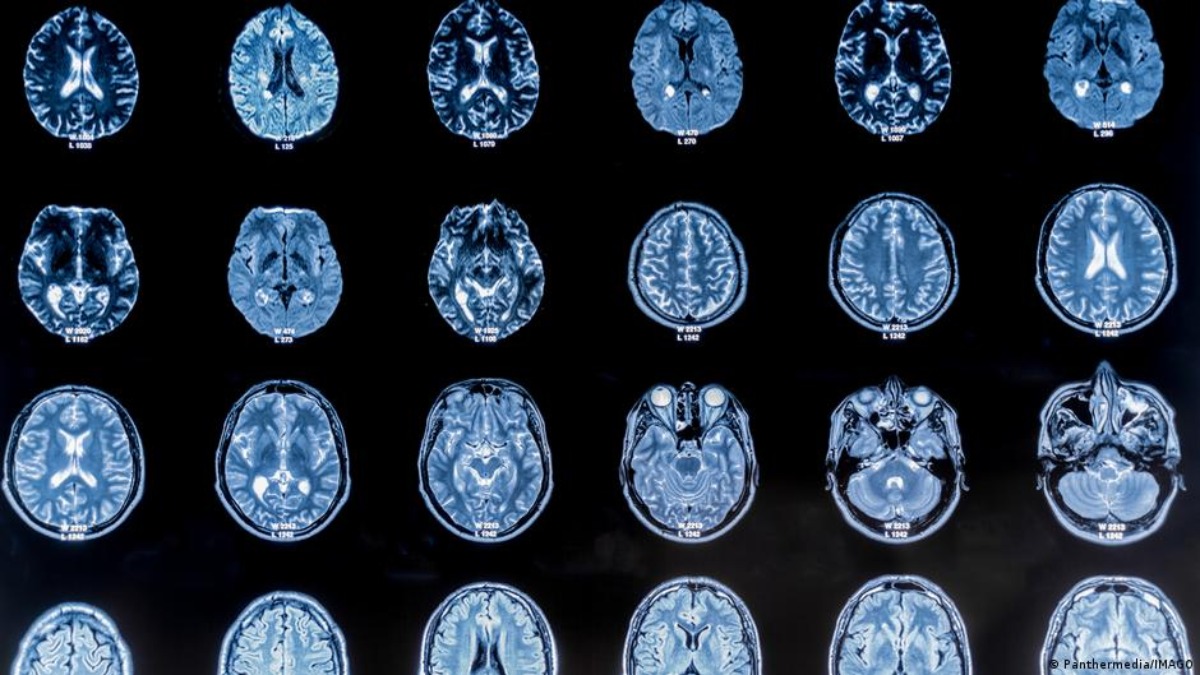

Istraživački tim sa Univerziteta Kembridž je analizirao 3.802 MRT snimka mozga i rekonstruisao obrasce neuronske povezanosti između rođenja i 90. godine. Podaci su otkrili iznenađujuće jasnu sliku: Strukturna organizacija mozga ne odvija se kontinuirano, već u pet glavnih faza od kojih je svaka obilježena značajnim prekretnicama – oko 9. 32. 66. i 83. godine.